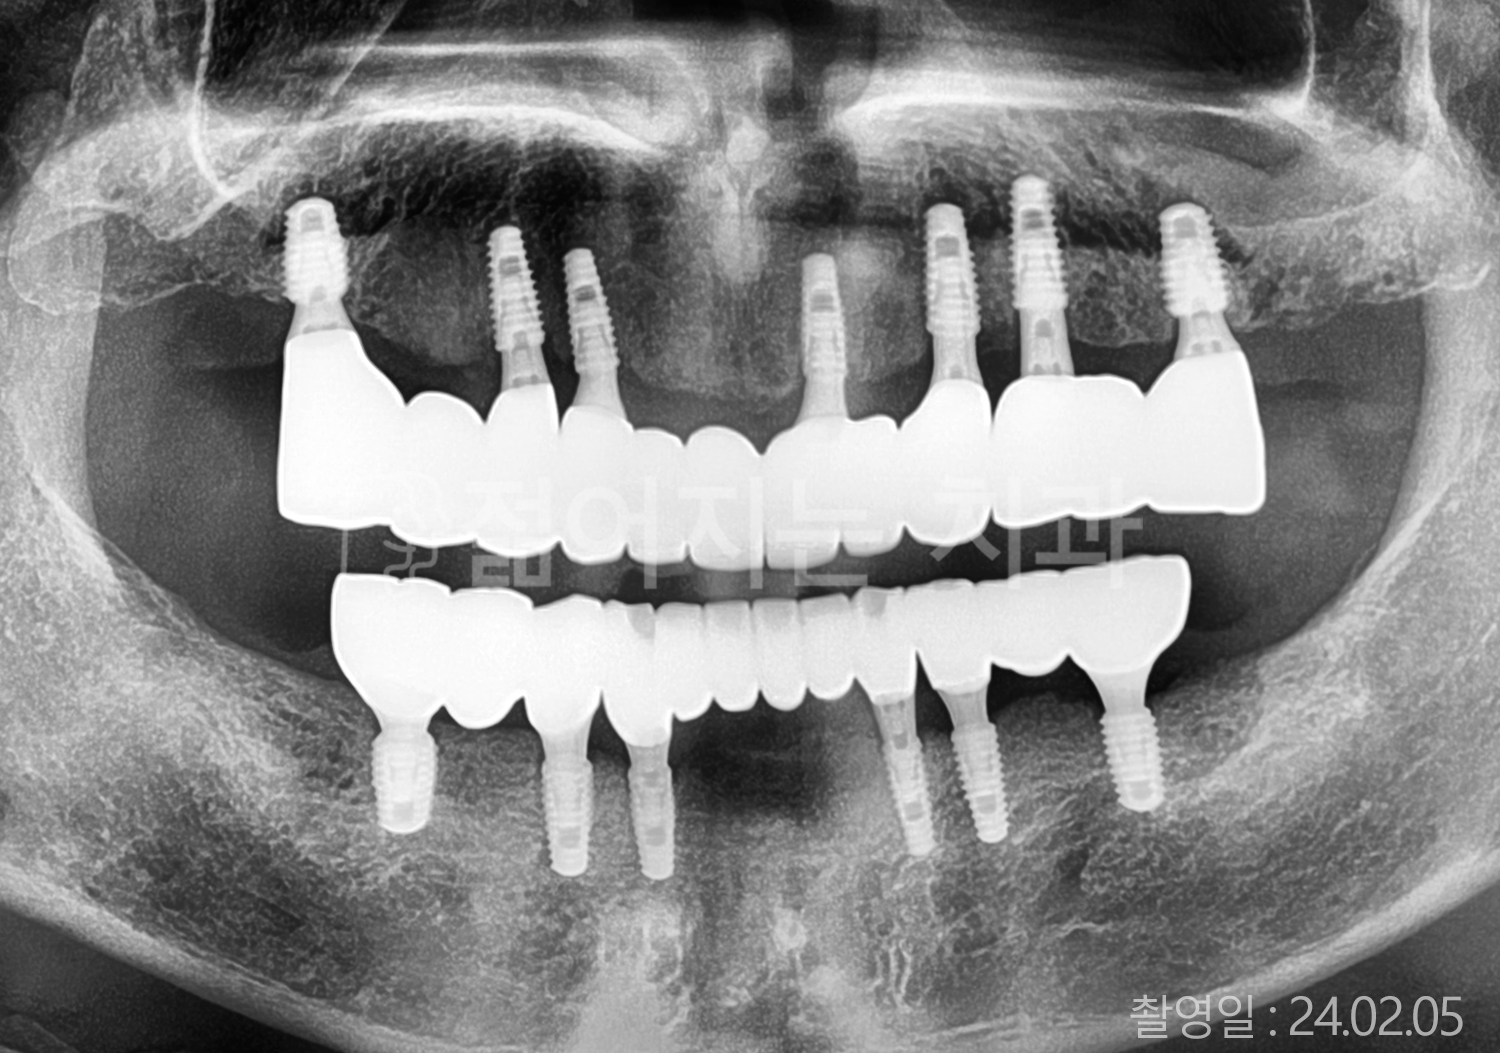

• 50대 전체치아 10개 이상 임플란트

• 50대 고혈압, 고지혈증 전체치아 10개 이상 임플란트

• 60대 고혈압, 당뇨, 고지혈증 전체치아 10개 이상 임플란트

• 70대 고혈압 전체치아 10개 이상 임플란트